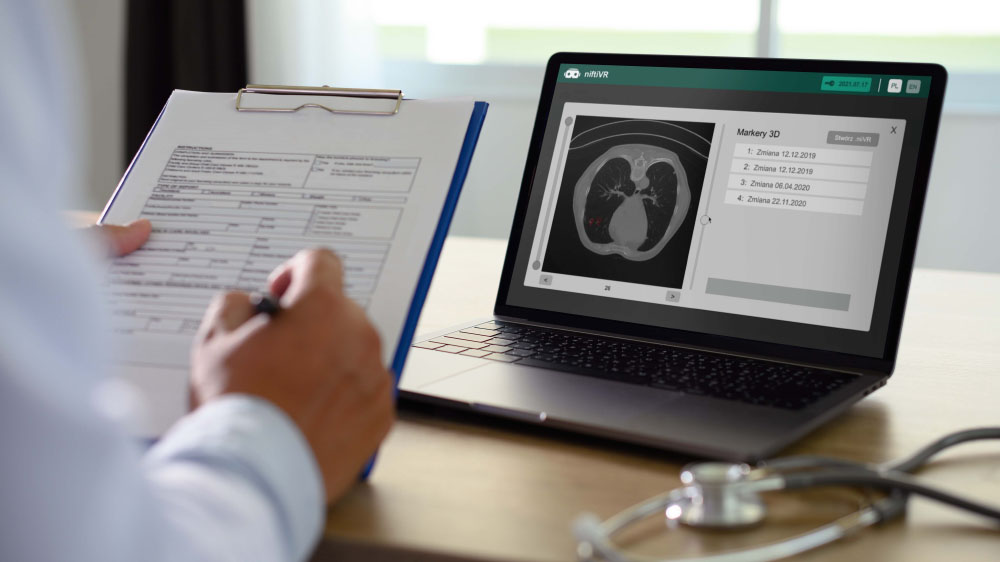

Preview of CT images from

brand new perspective

Profesional tool for doctors witch allowing analizing rentgen image analizing in VR

A modern program for analizing images from the tomograph

Thanks to our program, you will be able to manage lists of your patients in a quick and organized manner, saving time and more efficiently analyzing images from a computer tomograph or magnetic resonance imaging. The application allows you to load photos into the Virtual Reality environment, giving you the opportunity to view and analyze them in a new, unconventional way. Photos displayed in the form of 3D models can be freely rotated and viewed from different angles.